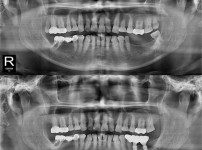

全口种植牙